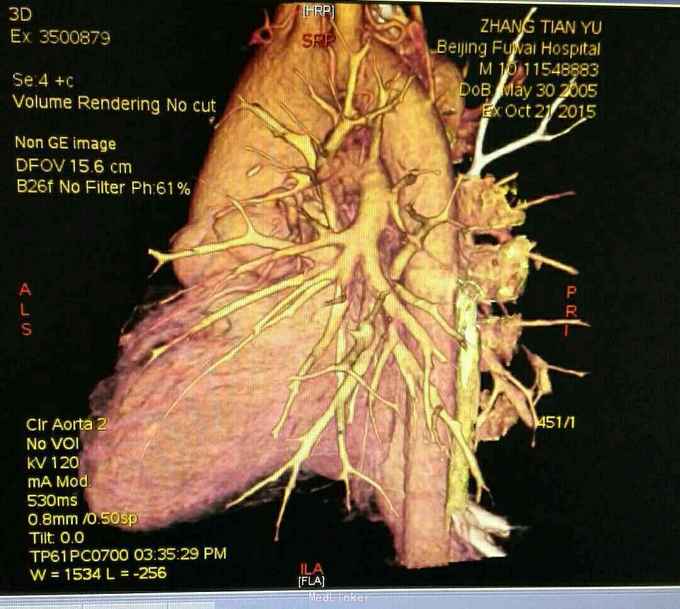

查体 生命体征平稳,口唇发绀,双肺呼吸音清,未闻及干湿性罗音,心律规整,于胸骨左缘可闻及杂音,腹部平软无压痛反跳痛,双下肢无水肿。 辅助检查 心脏彩超示 先天性心脏病 双向Glenn术后 单心室 大动脉转位 肺动脉瓣重度狭窄 上腔静脉-右肺动脉吻合口通畅。 心脏CT 先天性心脏病 双向Glenn术后 单心室 大动脉转位 肺动脉瓣重度狭窄 上腔静脉与右肺动脉连接。

诊断 先天性心脏病 双向Glenn术后 单心室 大动脉转位 肺动脉瓣重度狭窄。 治疗 患者入院后完善各项术前检查及准备,在全麻体外循环下行全腔静脉肺动脉吻合术,手术过程顺利,术后胸腔引流液增大,带胸骨8天引流液减少拔出引流管,患者顺利出院。 手术过程患者取仰卧位,常规消毒辅单,胸骨正中入路,小心分流心脏,建立体外循环,取人工血管将下腔静脉连接与肺动脉,同时结扎主肺动脉,辅助循环后减量停机,常规关胸安反监护室。